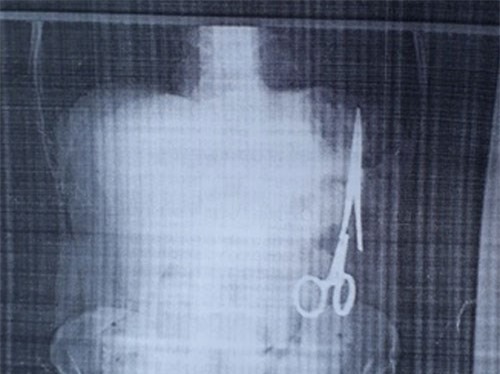

Theo người nhà bệnh nhân Ma Văn Nhật (SN 1962, trú tại xã Bình Trung, huyện Chợ Đồn, tỉnh Bắc Kạn), ca mổ đã diễn ra thành công, chiếc panh (kéo) dài 15cm đã được lấy ra khỏi bụng của bệnh nhân sau 1 tiếng 30 phút.

Liên quan đến vụ bác sĩ để quên kéo trong bụng bệnh nhân 18 năm, Bộ Y tế đã có yêu cầu Sở Y tế Bắc Kạn và Bệnh viện Đa khoa Tỉnh xác minh vụ việc.

Khi đi khám sức khỏe, một người đàn ông ở Bắc Kạn phát hiện trong ổ bụng có một chiếc kéo (panh) chuyên dụng, được cho là bác sĩ bỏ quên trong ca mổ cách đây 18 năm.

Cục Quản lý Khám chữa bệnh, Bộ Y tế cho biết sẽ xác minh, làm rõ việc Bệnh viện đa khoa Bắc Kạn để quên panh/kéo trong bụng bệnh nhân suốt 18 năm.

Mới đây, một bệnh nhân ở Bắc Kạn đi khám tại bệnh viện vô tình phát hiện ra một chiếc kéo phẫu thuật do bác sĩ để quên trong bụng 18 năm về trước.